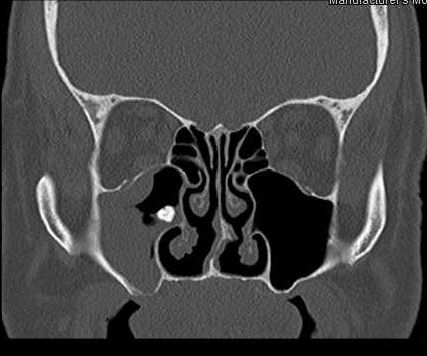

Distinguir radiográficamente un seno sano de uno enfermo no es tan problemático teniendo en cuenta su forma, que es inconsistente, con muchos lobulaciones, por lo tanto, en caso de sinusitis, se puede observar opacificación, engrosamiento de la mucosa y/o acumulación de líquido 17(Figura 3).

Diferentes estudios han demostrado que la SO podría representar entre el 45% y 75% de la opacificación unilateral del seno maxilar visibles en la TC 1,14,17.